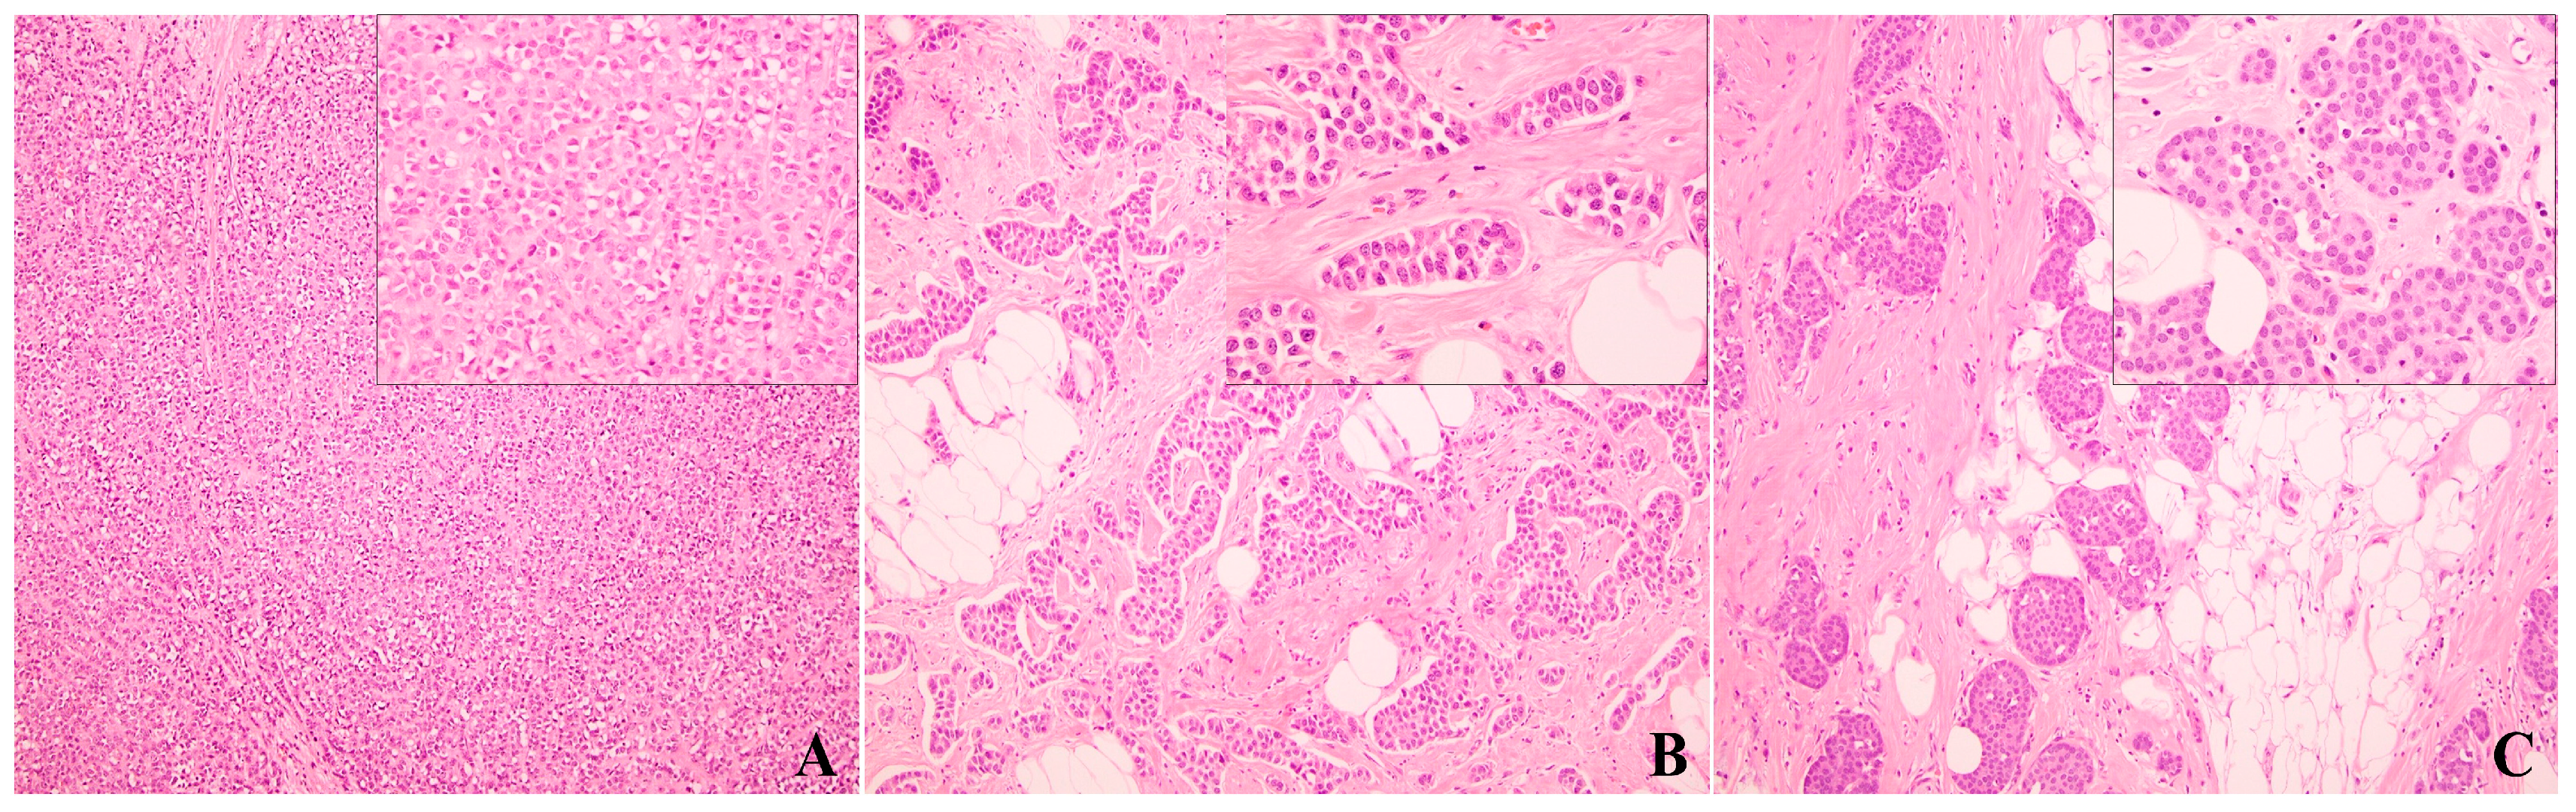

3.1. Classic Invasive Lobular Carcinoma

3.2. Histologic Variants of Invasive Lobular Carcinoma

3.3. Suboptimal Accuracy of Pathologic Classification of Invasive Lobular Carcinoma